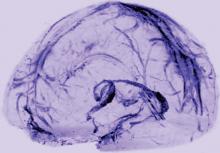

Researchers have visualized lymphatic vessels in the dura mater of humans on MRI, according to a short report published October 3, 2017, in eLife. They also have identified lymphatic vessels in brain tissue samples using immunostaining. The results suggest that the vessels could act as a pipeline between the brain and the immune system.

Dr. Reich and colleagues scanned the brains of five healthy volunteers who had been injected with gadobutrol, a dye used during MRI scans to visualize brain blood vessels. Gadobutrol that had leaked out of blood vessels in the dura as part of a normal process collected inside lymphatic vessels in the dura and showed up as bright white lines on MRI. “We watched people’s brains drain fluid into these vessels,” said Dr. Reich. When they repeated the experiment using a different dye that leaks much less out of blood vessels (ie, gadofosveset), the lymphatic vessels did not appear on imaging.

MRI showed collection of interstitial gadolinium within dural lymphatic vessels in all five of the healthy volunteers (ages 28 to 53, three women) and all three of the common marmoset monkeys studied. The vessels had a maximum apparent diameter of approximately 1 mm. “Our results suggest that in the dura, similar to many other organs throughout the body, small intravascular molecules extravasate into the interstitium and then, under a hydrostatic pressure gradient, collect into lymphatic capillaries through a loose lymphatic endothelium,” the researchers said. “On 3D rendering of subtraction MRI images, dural lymphatics are seen running parallel to the dural venous sinuses, especially the superior sagittal and straight sinuses, and alongside branches of the middle meningeal artery. The topography of the meningeal lymphatics fits with the previously described network in rodents.”

Although MRI shows large, slow-flow lymphatic ducts, “blind-ending and small lymphatic capillaries, clearly seen by histopathology, are unlikely to be revealed by MRI,” the researchers noted. In addition, they “could not prove whether dural lymphatic vessels drain immune cells, CSF, or other substances from the brain to deep cervical lymph nodes” or assess any link with the glymphatic system. “A comprehensive map of the meningeal lymphatic network would have implications for unraveling the ways in which the meningeal lymphatics participate in waste clearance and in immune cell trafficking within the CNS,” the researchers said.